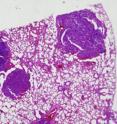

During the second year of life, both types of mice also developed pulmonary and hepatocellular (liver cell) tumors. Double knockout mice had a higher incidence of tumors than the single knockouts.